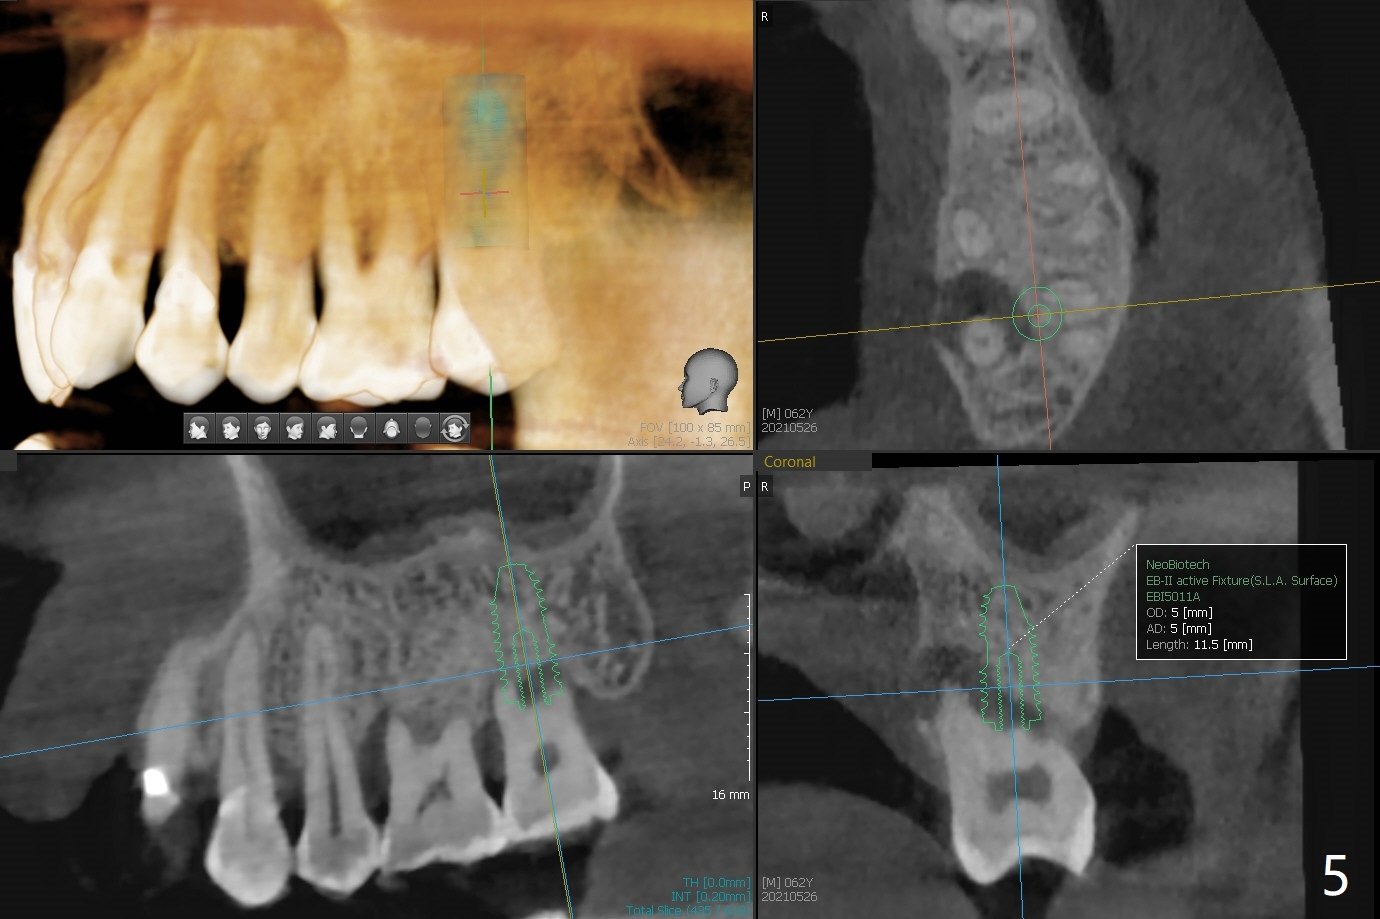

A 62-year-old man with sign of bruxism (#19 porcelain chip (Fig.2), 28 fracture/extraction) complains of severe mastication pain at #15 (Fig.1). More severe pain is elicited when the buccal cusps bite on a bite stick than the palatal one (Fig.3 with suspicious crazing lines). CT shows bone loss around the palatal root (Fig.4 P). A 5x11.5 mm implant will be placed immediately (Fig.5). The bone at #28 is able to hold a 3.5x13 mm implant (Fig.6). It is extremely difficult to take photos for 2nd molar crack line with a regular camera (Fig.3). The Shining Oral Scanner acts additionally as an intraoral camera. As a busy clinician, I do not have time to take photos for #19 porcelain chip. My assistants take over the task. After work, I am able to have bumper harvest. With the information just mentioned, I will be in a better position to present a more comprehensive treatment plan to the patient when treatment at #15 is finished: remove #18-20 bridge, place an implant at #19 and fabricate new crowns at #18 and 20.